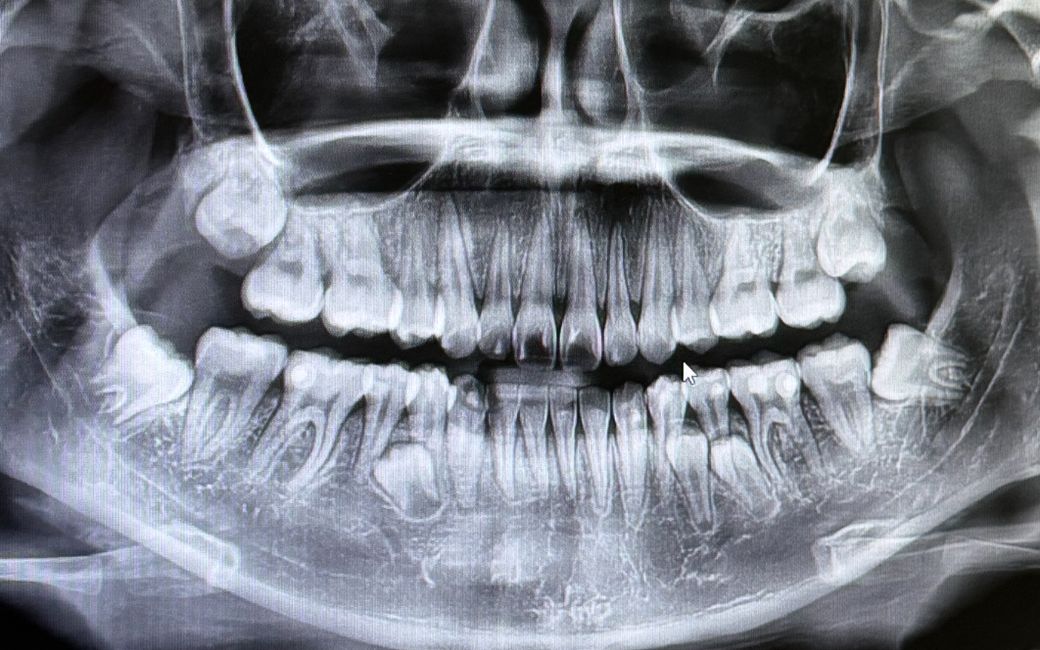

사랑니 이렇게 난 경우 뽑아야하나요?

사진처럼 사랑니가 있는데 4개 다 뽑아야하는 경우인가요? 아니라면 특정 뽑아야하는 이가 있을까요? 그리고 사랑니가 잇몸밖으로 안나오고 그냥 잇몸 안에 저상태 그대로 있을 수도 있나요?

사랑니 및 과잉치들 빼는 것이 좋겠습니다. 잇몸안에 있을 수도 있으나 안에서도 낭종이되는 등 문제가 생길 수 있습니다.

사랑니가 잇몸 안에 있다면 문제를 발생시킬 가능성이 적기 때문에 굳이 발치를 하지 않아도 됩니다 사랑니가 기울어져 있거나 부분적으로 맹출되었을 경우 치아의 충치를 유발하거나 치주질환을 유발할 수 있기 때문에 발치를 해 주는 것이 좋습니다.

사랑니가 앞의 어금니에 영향을 주고 있기에 이러한 사랑니는 빠른시일내에 발치를 하는 것이 앞의 어금니 손상을 막을 수 있습니다.

아직은 다 사랑니 맹출이 다 끝난상태가 아니라서 기다려 봐야겟지만 하악 사랑니는 발치를 해야될 가능성이 높아 보입니다.

아직 치근(뿌리)형성 및 맹출중인 것 같습니다. 사랑니는 20대 초반까지 맹출하게 되며 주변 치아나 잇몸뼈에 걸려있다면 더이상 나오지 못할 수도 있습니다.

지금 양상으로는 4개 다 옆 어금니에 영향을 줄 가능성이 있어 보입니다.